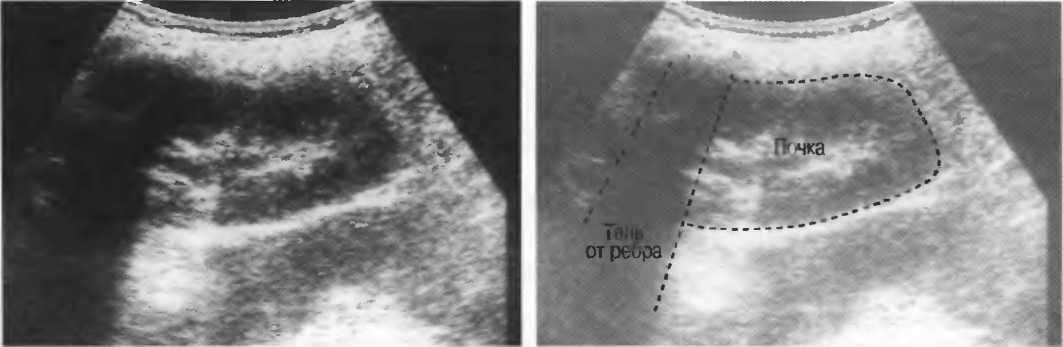

Плотные материалы, такие как кости или камни, дают акустическую тень на структуры, расположенные сзади, в результате того что ультразвуковая волна не проходит через них. Этот феномен получил название «акустической тени». Например, ребра могут экранировать ультразвуковой поток, поэтому структуры, расположенные за ними, нужно исследовать в косом направлении по межреберным промежуткам (рис. 10б,в).

Тени

Кости, камни и кальцинаты дают акустическую тень. Ультразвук не может проходить через кость, если она только не очень тонкая (как, например, кости черепа у новорожденного). При необходимости рассмотреть структуры, расположенные глубже, необходимо использовать различные углы наклона датчика (рис. 17а,б).

Рис. 176. Это изображение почки частично экранировано тенью ребра. Сканирование в различные фазы дыхания поможет визуализировать всю почку целиком, «вывести» ее из-под ребра.